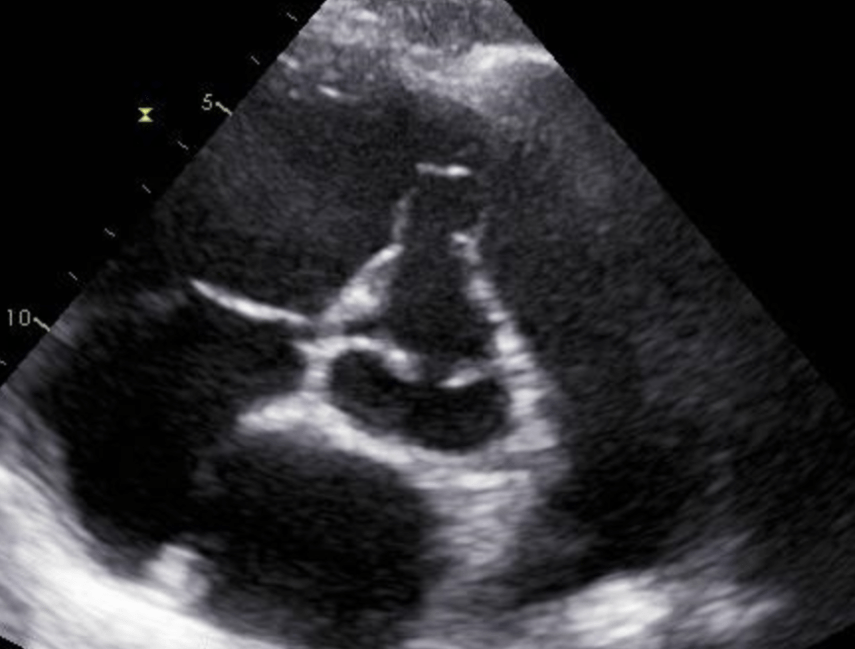

Cor triatrium

What is seen in the 2D image?

Eustachian valve